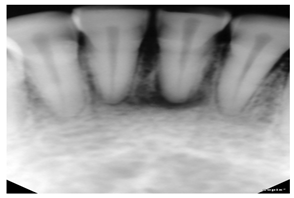

| Periapical X-rays | [12,39,40,59,86,87,88,89,90,91,92,93] | Diagnosing invisible proximal dental caries | ![]() | Display the entire tooth, from the crown to the root, where it connects to the jaw. |